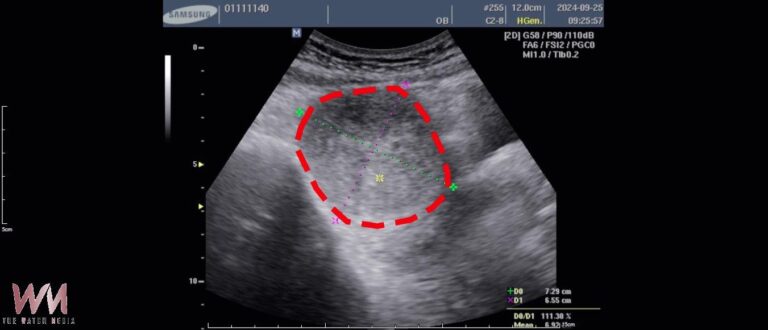

手術前:7.3×6.5×6.2公分。(圖/林新醫院…